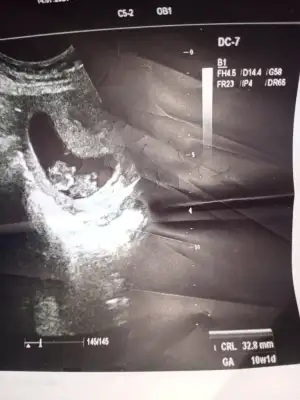

Benim bebeğime de bakar mısınız 9 buçuk haftalık. Belki erken ama bir yorumunuz olursa diye merak ediyorumEn iyi 11 12 13 haftalar olmalışimdilik erkek yönünde ama yanıltabilir dediğim haftalar olmalı

Şimdilik erkek yönünde ama en iyi 11 12 13 haftalar olmalı tekrar USG paylasinBenim bebeğime de bakar mısınız 9 buçuk haftalık. Belki erken ama bir yorumunuz olursa diye merak ediyorum

6haftalik 10 ve 11haftalik görüntüsü